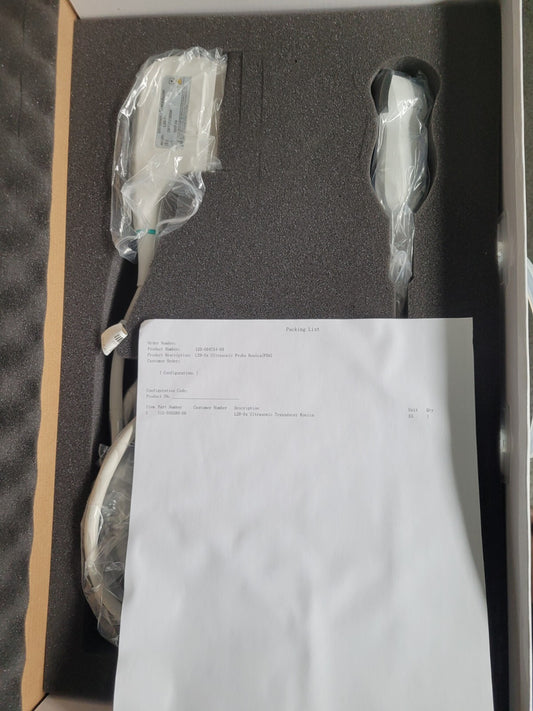

Mindray L14-6Ns Linear Ultrasound Transducer Probe (New)

Regular price $1,999.00 USDRegular priceUnit price / per -

Mindray L14-6Ns Linear Ultrasound Transducer Probe (New)

Regular price $2,499.00 USDRegular priceUnit price / per -